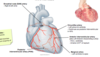

Most posterior structure- trachea, bifurcation into L and R main bronchi.

Most anterior is the superior vena cava, receiving the R and L brachiocephalic veins. The R and L brachiocephalic veins receive from the R and L internal jugular vein.

Middle structure - Arch of aorta, on R side brachiocephalic trunk which splits into the R subclavian and R common carotid. Splits into the L internal carotid and L subclavian.

Inferior stucture is the pulmonary trunk.

Ligamentous connection between the aorta and pulmonary trunk is called the ductus arteriosus. It fuses soon after birth- open in utero to bypass the deoxygenated blood past the lungs and straight into the aorta.

What happens if the ductus arteriosis remains open?

If the ductus arteriosus remains open this is called a patent ductus arteriosus and leads to mixing of deoxygenated blood and oxygenated blood.

This can put a strain on the heart and increase blood pressure in lung arteries.